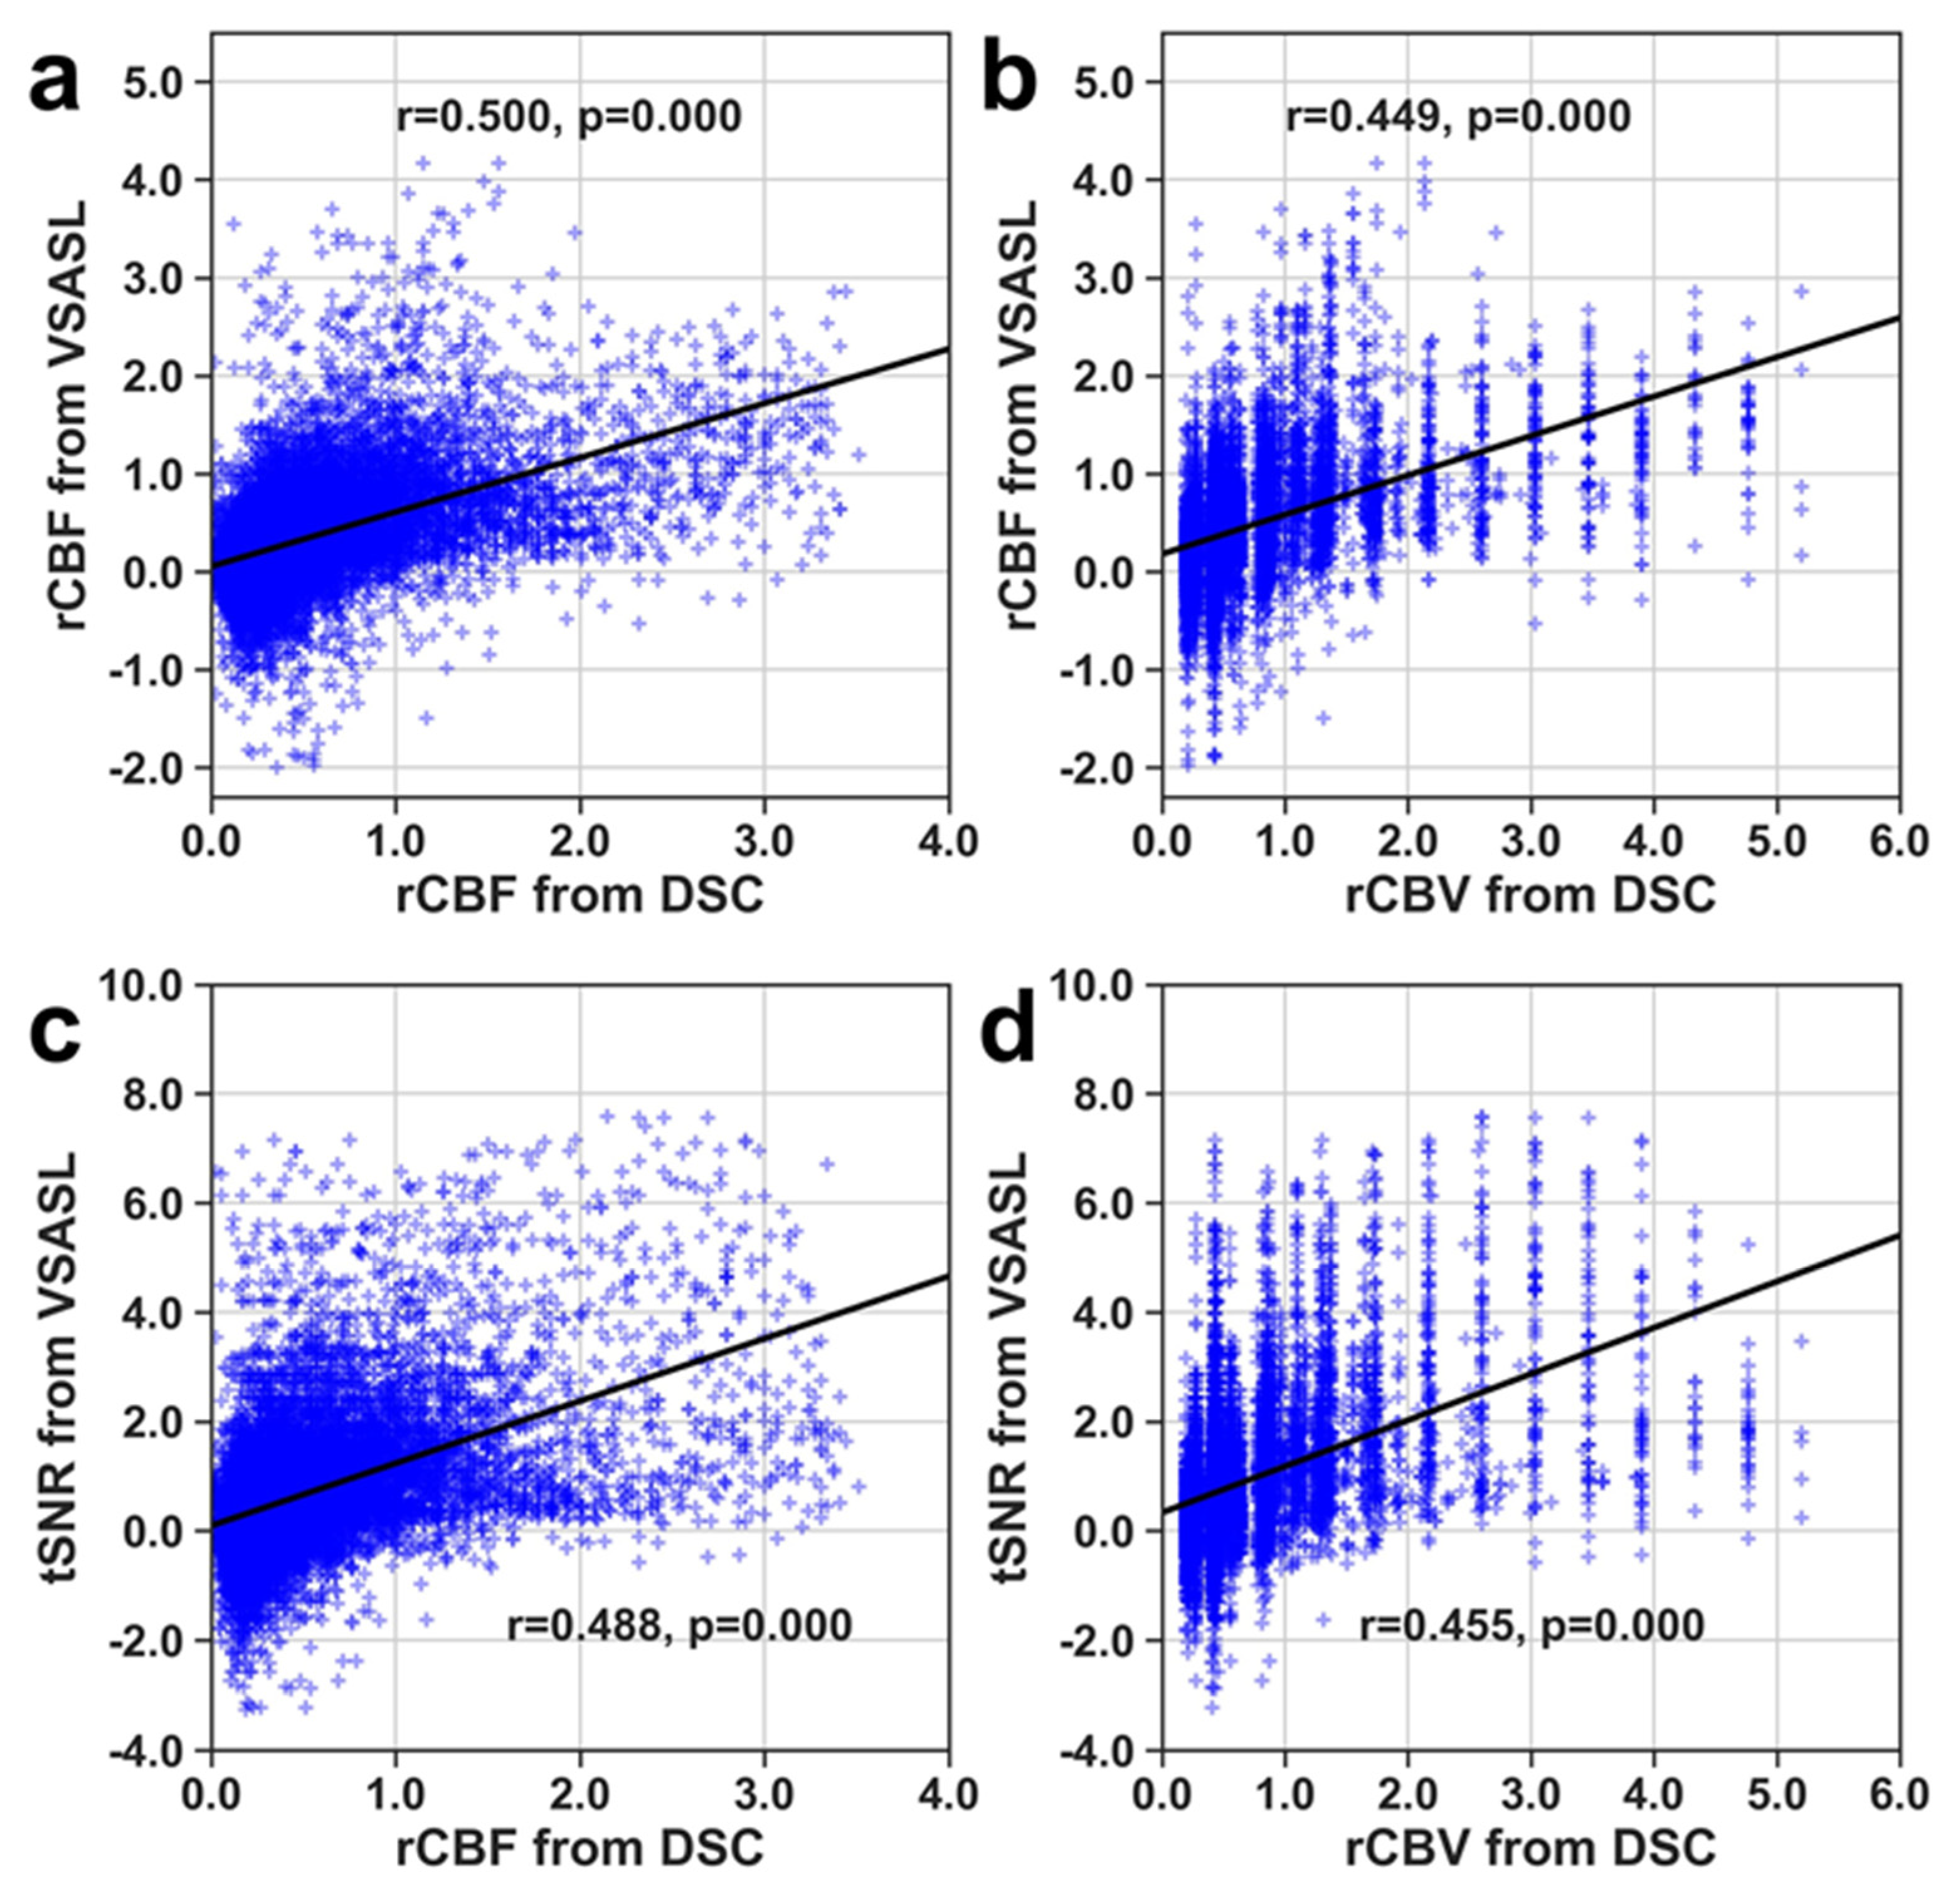

3. Results